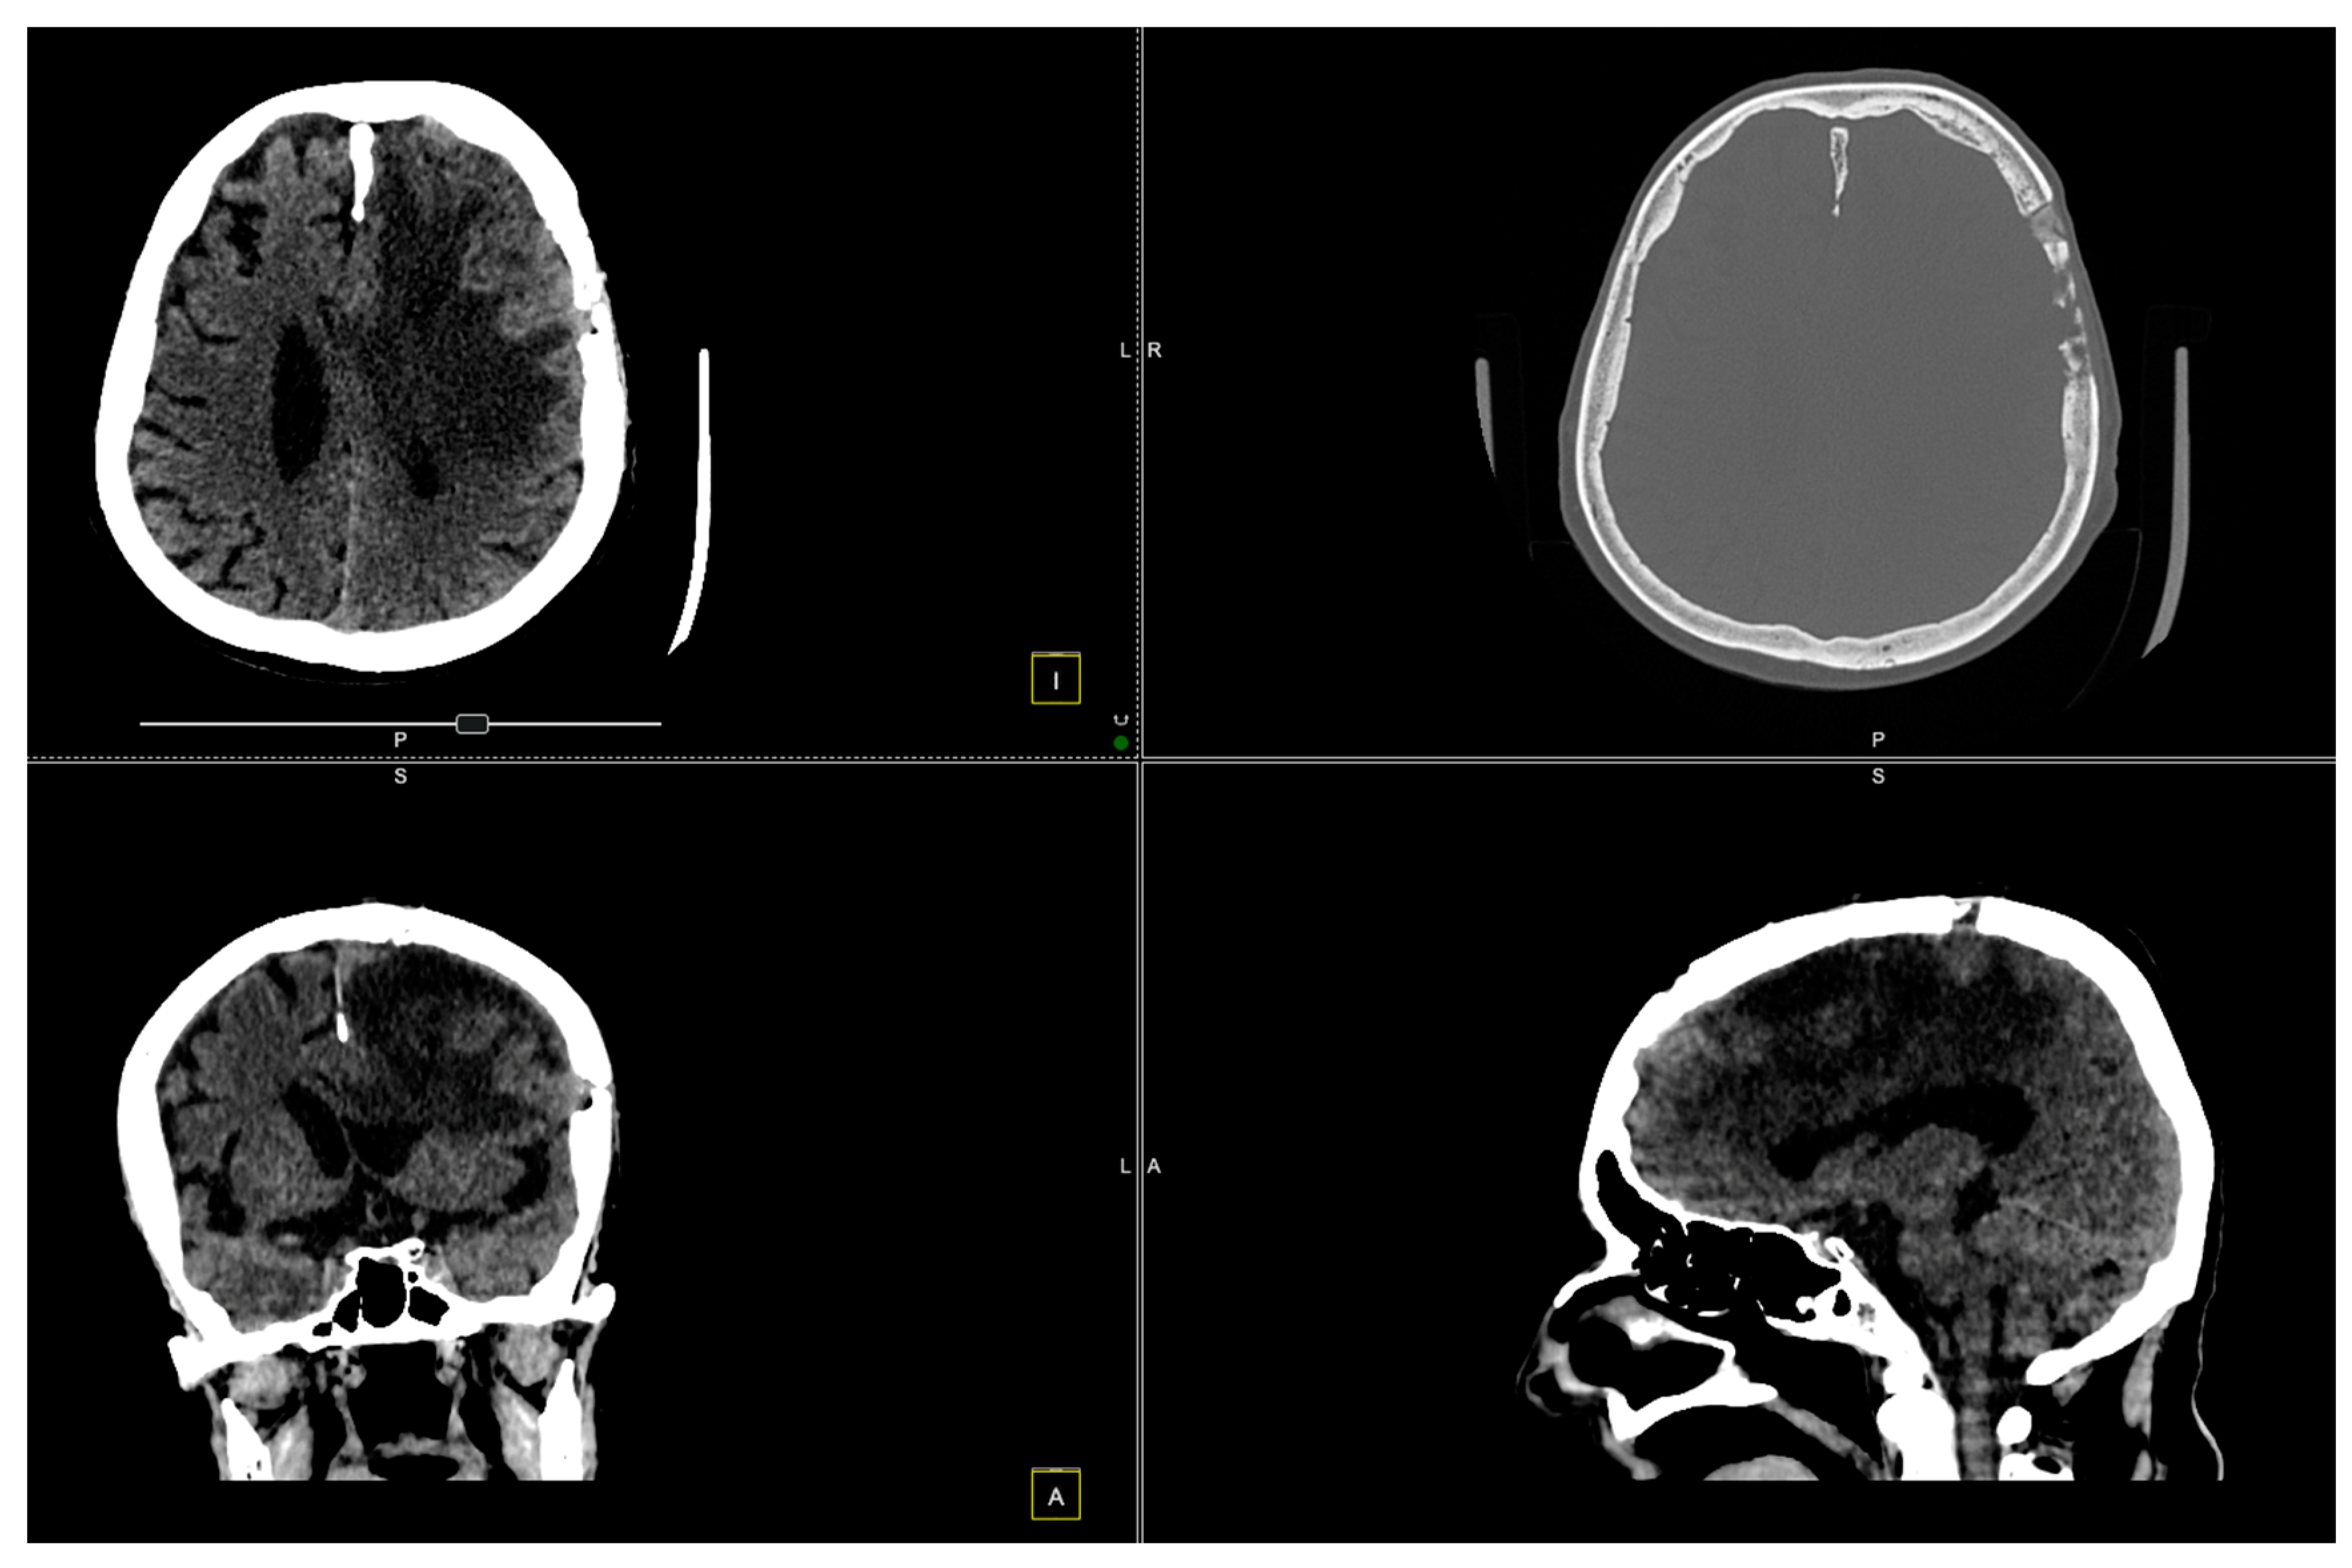

2. Case Presentation